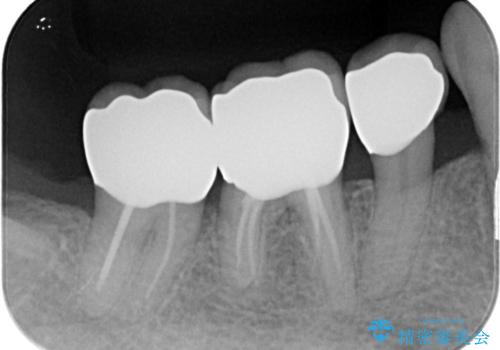

- 他院にて以前治療した修復物の下に虫歯を認めたため、オールセラミックにて修復治療を行なっております。